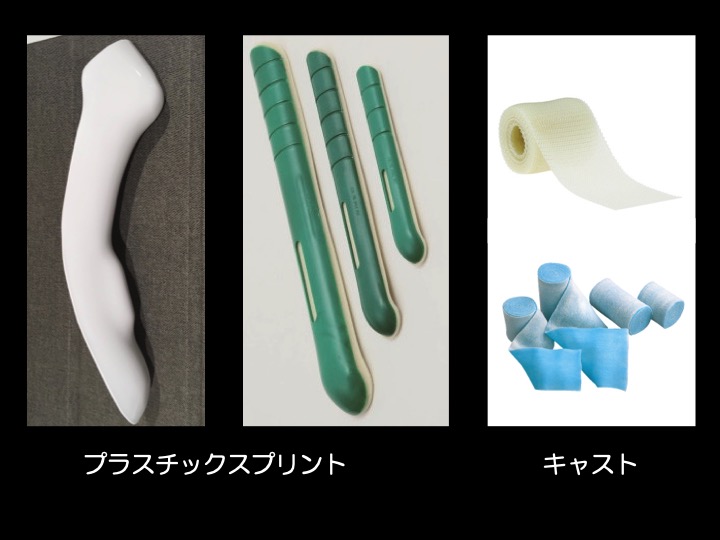

【ギプス(外固定)】

・骨折による骨のズレが小さい場合などが適応となります。

・手術前後の一時的な固定として使用されることもあります。

・多くの場合、全身麻酔を必要としません。